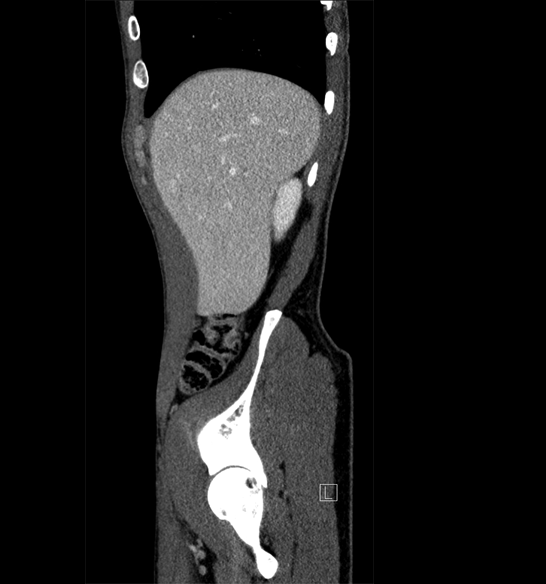

Body

Covers abdominal CT anatomy.